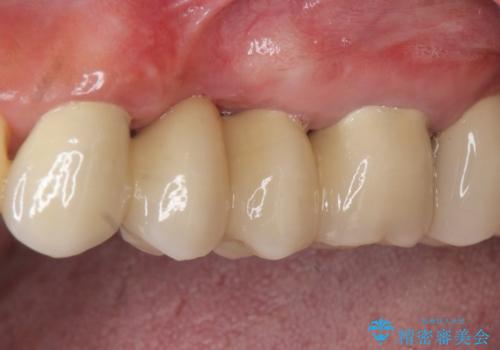

歯周病 側方力に対抗するブリッジ補綴

歯列不正による第一小臼歯の骨吸収が認められ、機能咬合力の回復、大きな側方力に連結することで抵抗することのできるブリッジ補綴を選択しました。

- 32万円(仮歯・フルジルコニアクラウン×4)費用は治療当時の料金となります

歯周病による深いポケット・大きな側方力・短い臨床歯根・欠損の補綴、これらの問題を解決するために歯周補綴を兼ねたブリッジを選択しました。